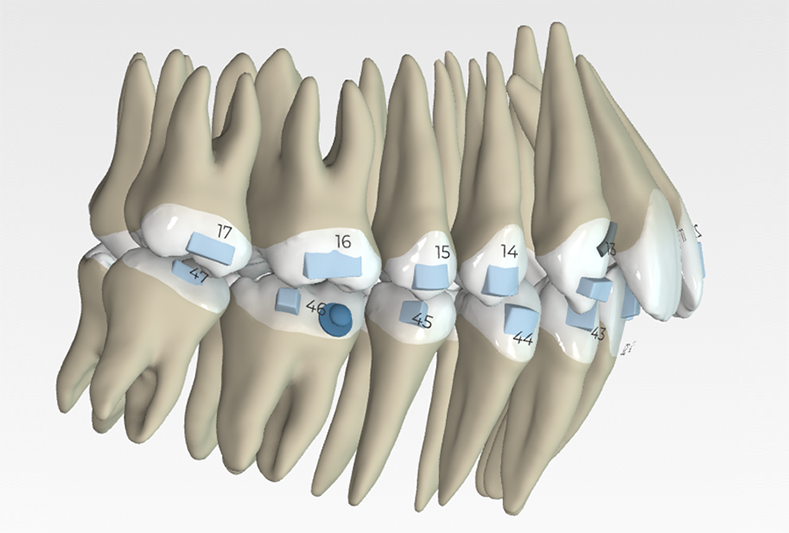

Upper arch: 20 active aligners

Transverse expansion

Derotation with mesial-out of first molars

Space opening for 12 by distalizing 13

Maxillary midline correction

Lower arch: 31 active aligners

Incisor intrusion using frog staging

Vertical attachments on lower incisors for improved tipping control

Space opening for 31 and 41

Elastics protocol

Class II elastics: 4.5 oz, 14 hours/day

Hooks on 13 and 23, button cut-outs on lower molars

Wear Schedule: Aligners 1–2: 10 days each and remaining aligners: 7 days each